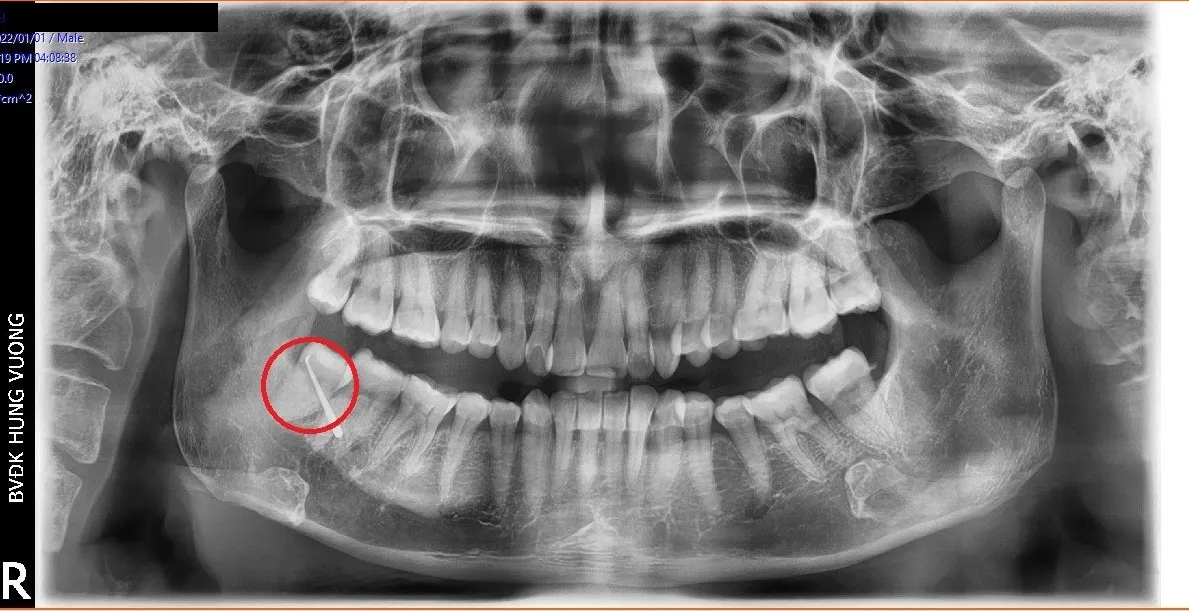

Đến Bệnh viện đa khoa Hùng Vương (Phú Thọ) thăm khám, bệnh nhân được chỉ định nhập viện điều trị ngay với chẩn đoán: Áp xe vùng má phải do răng số 48 mọc lệch.

Hy hữu: Bệnh nhân bị... thủng má do biến chứng răng số 48 mọc lệch - Ảnh 1.